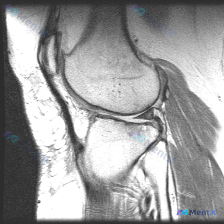

本次分析基于一张膝关节矢状位T1加权磁共振图像,临床提示存在「chondral abnormality(软骨异常)」,无其他病史、体征或检验结果提供。

影像基本观察(单张T1序列)

先给大家整理下这张图像能看到的信息:

- 骨性结构:股骨远端、胫骨近端骨髓信号均匀,骨皮质边缘完整,软骨下骨质边缘光滑,没有明显缺损、囊变或破坏

- 半月板与韧带:该层面半月板形态完整,没有看到信号中断或穿透关节面的异常高信号;后交叉韧带连续性良好,走行自然

- 关节与软组织:髌下脂肪垫信号均匀,关节腔没有看到明显积液,腘窝及周围软组织没有异常占位

- 软骨观察:股骨髁、髌骨的关节软骨面轮廓尚清晰,这张T1序列上没有看到明确的局灶性变薄、缺损或信号异常

总结:仅从这张单层面T1图像看,没有发现明确的结构性异常